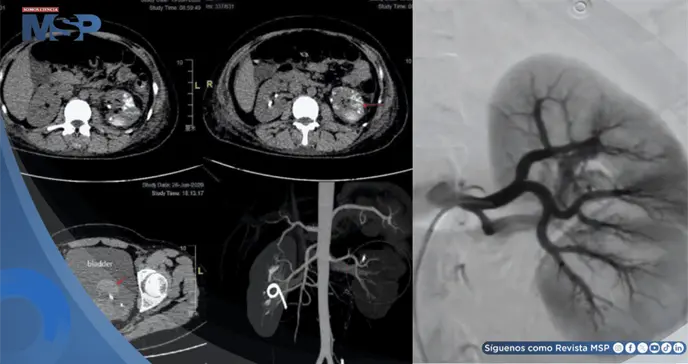

Este hallazgo se confirmó mediante angiografía por sustracción digital (DSA), la cual mostró una arteria renal izquierda dilatada y tortuosa que formaba una masa vascular, con opacificación precoz de la vena renal y la vena cava inferior en la fase arterial.

Se realizó una embolización urgente mediante cateterismo selectivo de la arteria renal izquierda. El procedimiento consistió en la oclusión con partículas de esponja de gelatina (560–710 µm) reforzada con tres resortes helicoidales. La DSA de control confirmó la eliminación exitosa de la derivación arteriovenosa.

Sin embargo, dos días después, una tomografía computarizada (TC) reveló múltiples lesiones de alta densidad en el parénquima renal izquierdo y líquido libre en la cavidad pélvica, indicando sangrado residual. La paciente fue dada de alta al octavo día post-embolización.